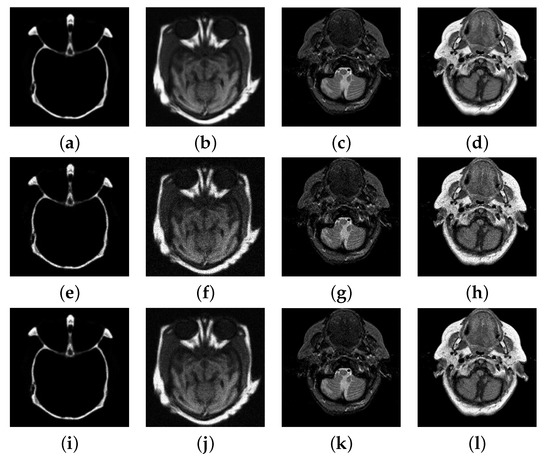

4.3. Numerical Experimental Results and Analysis

| Test Images | Peak | Noisy | PSNR | |||

|---|---|---|---|---|---|---|

| Multifocus1 | 155 | 25.97/25.72 | 28.02/27.50 | 4.00 | 0.40 | 0.39 |

| 255 | 28.17/27.87 | 29.13/28.35 | 4.58 | 0.39 | 0.41 | |

| Multifocus2 | 155 | 25.39/25.41 | 29.72/30.16 | 4.71 | 0.54 | 0.70 |

| 255 | 27.57/27.56 | 30.43/30.55 | 4.77 | 0.60 | 0.66 |